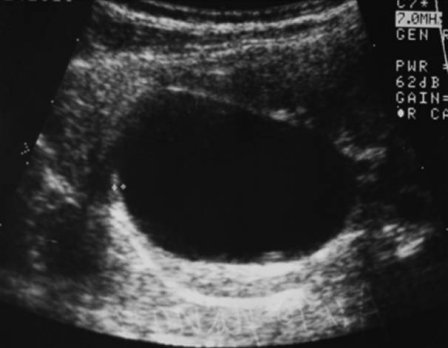

Основной метод диагностики — УЗИ с допплерографией, позволяющее локализовать кисту, определить её размеры, соотношение с коллекторной системой почки, и характер кровотока в паренхиме окружающей кистозную полость (рис. 1 а, б). С помощью УЗИ при диспансерном наблюдении у больных с солитарной кистой почки оценивают размеры кисты по мере роста ребёнка.

Рис. 1. Киста верхнего полюса почки. Ультразвуковая сканограмма. а) в В-режиме, б) энергетическое допплеровское картирование.